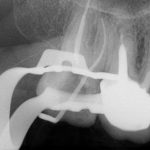

- Depois de anestesia e isolamento absoluto, realizamos o acesso endodôntico com uma broca de alta rotação 1014 de haste longa, utilizada em contra ângulo elétrico. O acesso aos canais foi complementado com inserto ultrassônico esférico com a finalidade de desgastar pouca estrutura dental para localizar os canais.

- Logo, o sistema escolhido para a instrumentação dos canais vestibulares foi o TruNatomy, por causa de sua atresia e curvatura. Para a instrumentação inicial foi usada a lima de pré-alargamento TruNatomy Orifice Modifier e após isso, uso de limas C pilot 8, 10 e 15.

- Após a odontometria eletrônica, utilizou-se a lima TruNatomy para Glidepath.

- Então, para a modelagem nos canais vestibulares, utilizou-se as limas 20.04 e 26/04 (Figura 4).

Figura 2 Figura 3 Figura 4 Figura 5 Figura 6 Figura 7